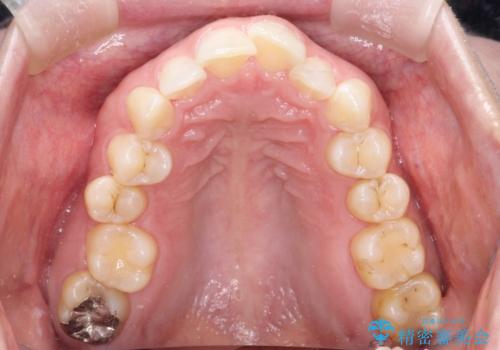

【インビザライン】前歯の凸凹を治したい。

- 前歯の凸凹を主訴に来院されました。

深い噛み合わせも同時に治療を行う計画を立て、インビザラインを使用して歯並びの改善を行うことができました。

叢生改善のために遠心移動とIPRを行なっています。